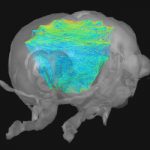

With prolonged aging, medicine is facing considerable challenges. In this fight against diseases, creating new imaging and therapy tools is essential for an increased understanding of pathologies and an improved patient care. Our institute Physics for Medicine Paris, also known as Institut Physique pour la Médecine, is a French research unit (Inserm/ESPCI Paris-PSL/CNRS) gathering physicists experts in ultrasound waves. We invent innovative technologies for medical imaging and therapy, which translate to three main field of medicine: cancer, cardiovascular diseases and neurosciences.